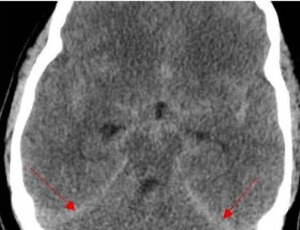

Central Nervous System (CNS) Vasculitis in a Patient with Systemic Lupus Erythematosus (SLE) and Lupus Nephritis: A Case Report

Systemic lupus erythematosus (SLE) is characterized by diverse symptoms including fever, joint pain, facial rash, blood in urine, and sores in the mouth. Neuropsychiatric SLE (NPSLE) refers to neurological and psychiatric manifestations in SLE patients after exclusion of other potential causes. A 21-year-old woman with established lupus nephritis presented with left-sided weakness, aphasia, confusion and focal neurological deficits. Imaging studies demonstrated multiple infarcts and central nervous system (CNS) vasculitis.